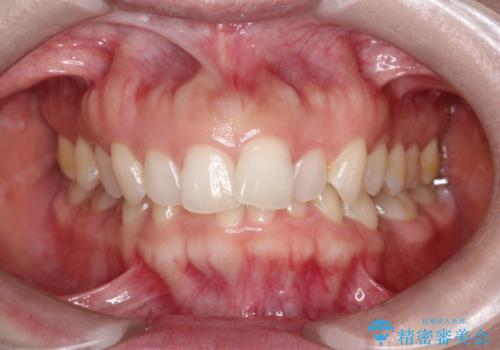

【インビザライン】前歯の凸凹を治したい。

- 前歯の凸凹を主訴に来院されました。

深い噛み合わせも同時に治療を行う計画を立て、インビザラインを使用して歯並びの改善を行うことができました。

叢生改善のために遠心移動とIPRを行なっています。